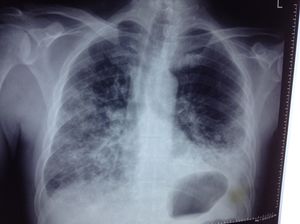

Diabetic pt € dyspnea

Failure

Congestive Heart Failure